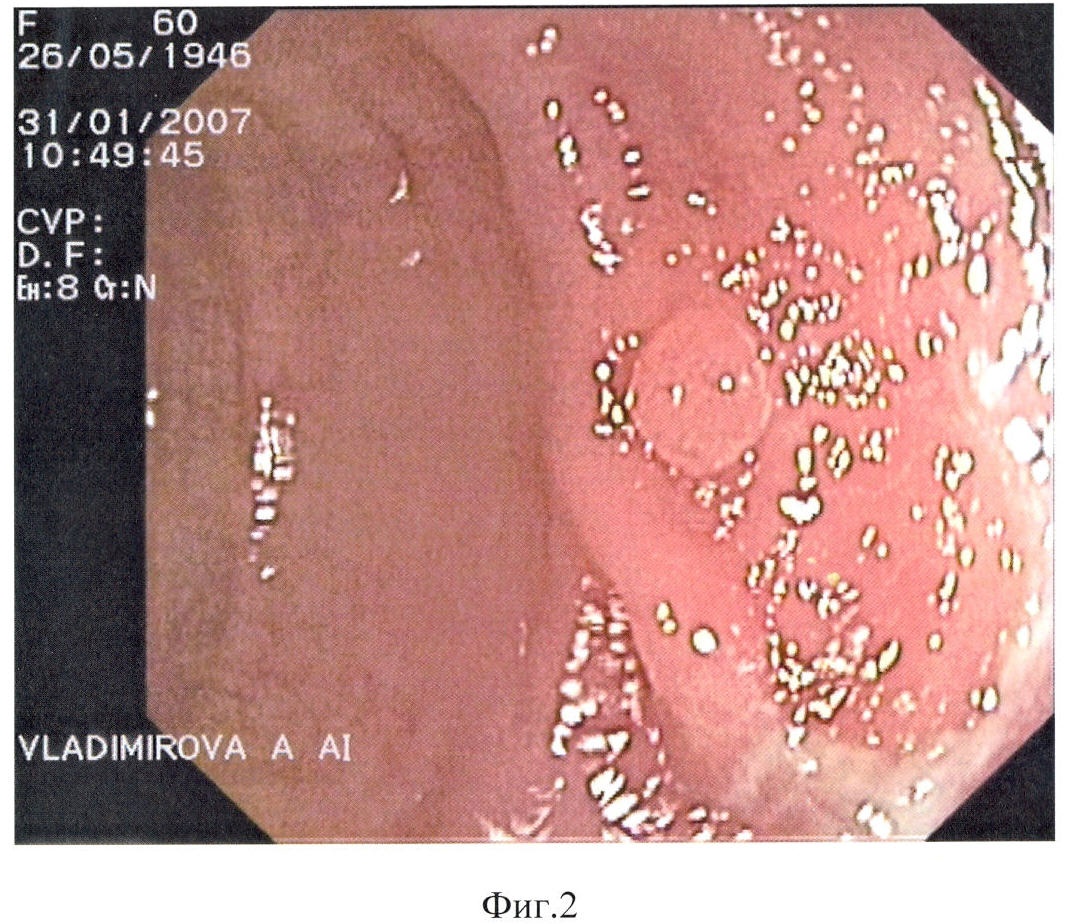

Способ поясняется следующими чертежами, где на фиг.1 показан полип области печеночного изгиба, суммарный балльный критерий более 179: а – при максимальном приближении дистальной головки и линзы колоноскопа, б – после биопсии; на фиг.2 – полип сигмовидной кишки, суммарный балльный критерий до 178 баллов (клинический пример 1); на фиг.3 – полип сигмовидной кишки, суммарный балльный критерий более 179 баллов, на фиг.4 – гистологический срез полипа сигмовидной кишки, окраска гематоксилин-эозином (клинический пример 2); на фиг.5 – полип сигмовидной кишки, суммарный балльный критерий до 178 баллов, на фиг.6 – полип сигмовидной кишки через 10 месяцев после первого обследования, суммарный балльный критерий более 179 баллов (клинический пример 3), а также табл.1, где перечислены эндоскопические признаки, их градации и числовые значения, используемые для вычисления суммарного балльного критерия, и табл.2, где показана морфологическая характеристика полипа и лечебная тактика в зависимости от суммарного балльного критерия исследования.

Последняя контрольная колоноскопия выполнена 31.02.2007 г. Толстая кишка осмотрена до купола слепой кишки. Баугиниева заслонка губовидной формы, розовая. Просвет толстой кишки хорошо расправляется воздухом. Тонус кишечной стенки не снижен, перистальтика прослеживается. Слизистая толстой кишки розовая, сосудистый рисунок просматривается хорошо на всем протяжении.

В нижней трети сигмовидной кишки расположен полушаровидный полип до 0,2 см в диаметре, розовый, гладкий, не реагирует на инструментальную пальпацию (фиг.2).

По выявленным признакам вычислен суммарный балльный критерий:

Критерий = группа по размеру + эндоскопический тип + цвет + форма + поверхность + ранимость = 21+44+17+12+12+7=113 баллов.

В соответствии с предложенным авторами критерием было дано заключение о наличии доброкачественного морфологического строения полипа. Взята биопсия. При гистологическом исследовании – гиперпластический полип.